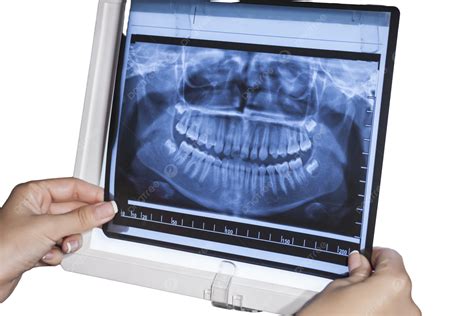

When you step into a dental office for a comprehensive examination, your dentist often suggests advanced imaging to get a complete picture of your oral health. One of the most common and vital tools in modern dentistry is the Panoramic Dental X Ray. Unlike standard bitewing or periapical X-rays that focus on one or two teeth, this imaging technique captures the entire mouth in a single, sweeping image. This includes the upper and lower jaws, all the teeth, the temporomandibular joints (TMJ), and even the surrounding sinus structures, providing a holistic view that is indispensable for accurate diagnosis and treatment planning.

The Panoramic Dental X Ray utilizes a specialized machine called an orthopantomogram (OPG). During the procedure, the X-ray tube and the digital sensor rotate in a semicircular motion around your head, capturing a continuous image of your dental anatomy. Because the human jaw is curved, the machine is calibrated to track this arc, ensuring that all dental structures remain in focus throughout the rotation.

This technology is revolutionary because it eliminates the need for placing multiple small sensors inside your mouth, which can be uncomfortable for patients with a sensitive gag reflex. By capturing the entire maxillofacial region, dentists can identify conditions that might otherwise remain hidden beneath the gum line or deep within the jawbone.